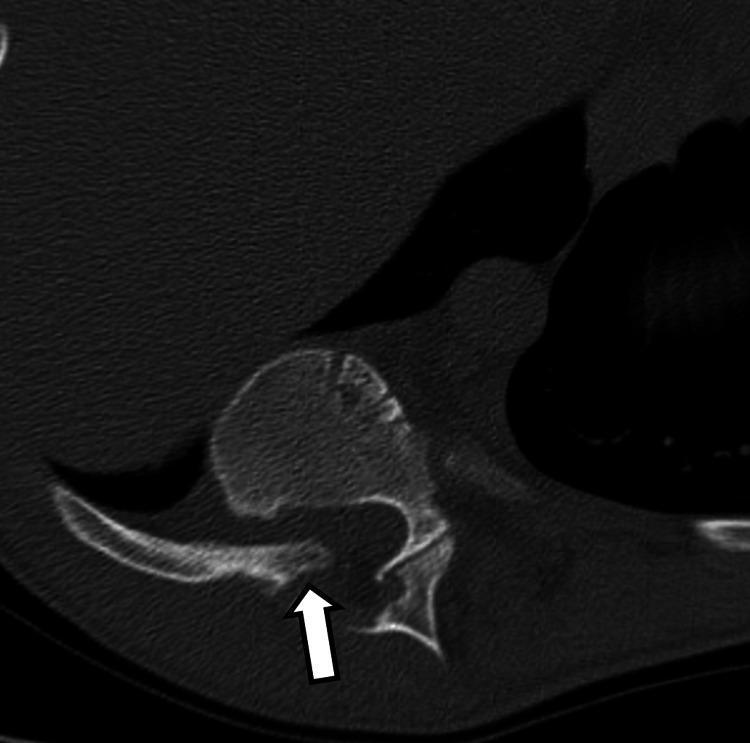

Neurofibromatosis type 1 (NF1) is frequently associated with a multitude of skeletal abnormalities including dystrophic scoliosis. A rare but severe complication of dystrophic scoliosis in NF1 is the herniation of rib heads into the spinal canal, potentially leading to devastating spinal cord compression. We present two pediatric cases of NF1-associated dystrophic scoliosis with intra-spinal herniation of rib heads. Case 1 involves a teenage male with progressive thoracolumbar scoliosis and protrusion of T10 and T11 rib heads into the spinal canal, who underwent successful posterior spinal fusion (T3-L3) with instrumentation, osteotomies, and rib head resection. Case 2 involves a teenage female with progressive thoracolumbar scoliosis and intra-spinal protrusion of T4 and T5 rib heads, who remains neurologically intact despite worsening curvature. Intra-spinal herniation of rib heads is a clinically important complication of NF1-associated dystrophic scoliosis requiring close surveillance. Familiarity with this complication is important as imaging findings may be subtle early on. Surgical management typically involves both spinal fusion and resection of rib heads to prevent neurological compromise, though timing may vary based on symptoms and progression. Multidisciplinary care is essential.

1型神经纤维瘤病(NF1)常伴有多种骨骼异常,包括营养不良性脊柱侧凸。NF1中营养不良性脊柱侧凸的一种罕见但严重的并发症是肋骨小头疝入椎管,可能导致毁灭性的脊髓压迫。我们报告两例NF1相关的营养不良性脊柱侧凸伴肋骨小头椎管内疝的儿科病例。病例1为一名青少年男性,患有进行性胸腰椎脊柱侧凸,T10和T11肋骨小头突入椎管,接受了成功的后路脊柱融合术(T3-L3),包括器械固定、截骨术和肋骨小头切除术。病例2为一名青少年女性,患有进行性胸腰椎脊柱侧凸,T4和T5肋骨小头椎管内突出,尽管脊柱侧凸加重,但神经功能仍保持完好。肋骨小头椎管内疝是NF1相关的营养不良性脊柱侧凸的一种重要临床并发症,需要密切监测。熟悉这种并发症很重要,因为早期影像学表现可能很细微。手术治疗通常包括脊柱融合和肋骨小头切除,以防止神经功能受损,不过手术时机可能因症状和病情进展而异。多学科护理至关重要。